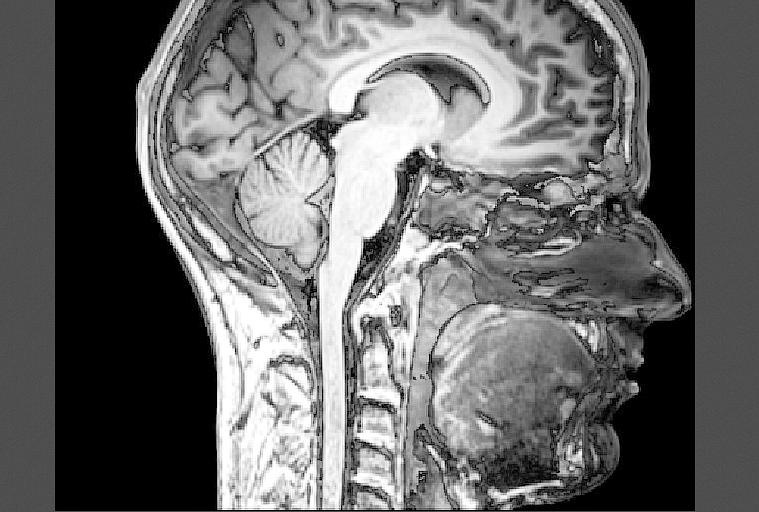

Instituir no município o programa de conscientização Julho Verde, dedicado a ações educativas para prevenção do câncer de cabeça e de pescoço, é a proposta de lei da vereadora Noemia Rocha (MDB) apresentada na Câmara Municipal de Curitiba (CMC). Anualmente, neste mês, deveriam ser realizadas atividades acerca  dessas doenças, que representam 3% dos tumores malignos identificados (005.00189.2019).

A escolha do mês de Julho para o projeto, de acordo com a justificativa, foi realizada devido ao Dia Mundial do Câncer de Cabeça e Pescoço ser 27 de julho, conforme definido em Congresso Mundial sobre o assunto em 2014. Para realização do Julho Verde o texto da proposição prevê a possibilidade de cooperação do poder público com a iniciativa privada e outros setores da sociedade civil para realizar campanhas educativas e preventivas, com objetivo de combater o câncer de cabeça e pescoço.